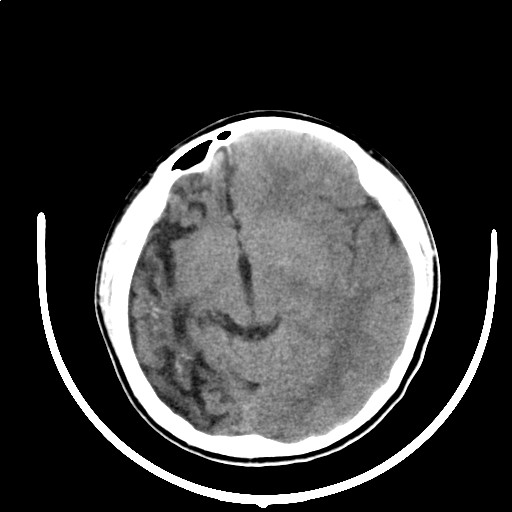

标题: PED3416:F,12Y,智力下降,学习成绩差,8个月时发过高烧。

右侧半球萎缩,软化,多量脑回样钙化,考虑颅面血管瘤病,建议dsa检查

右侧半球萎缩,软化,多量脑回样钙化,同侧颅盖板障增宽,考虑颅面血管瘤病,建议dsa检查与化脓性脑膜炎后遗改变鉴别。